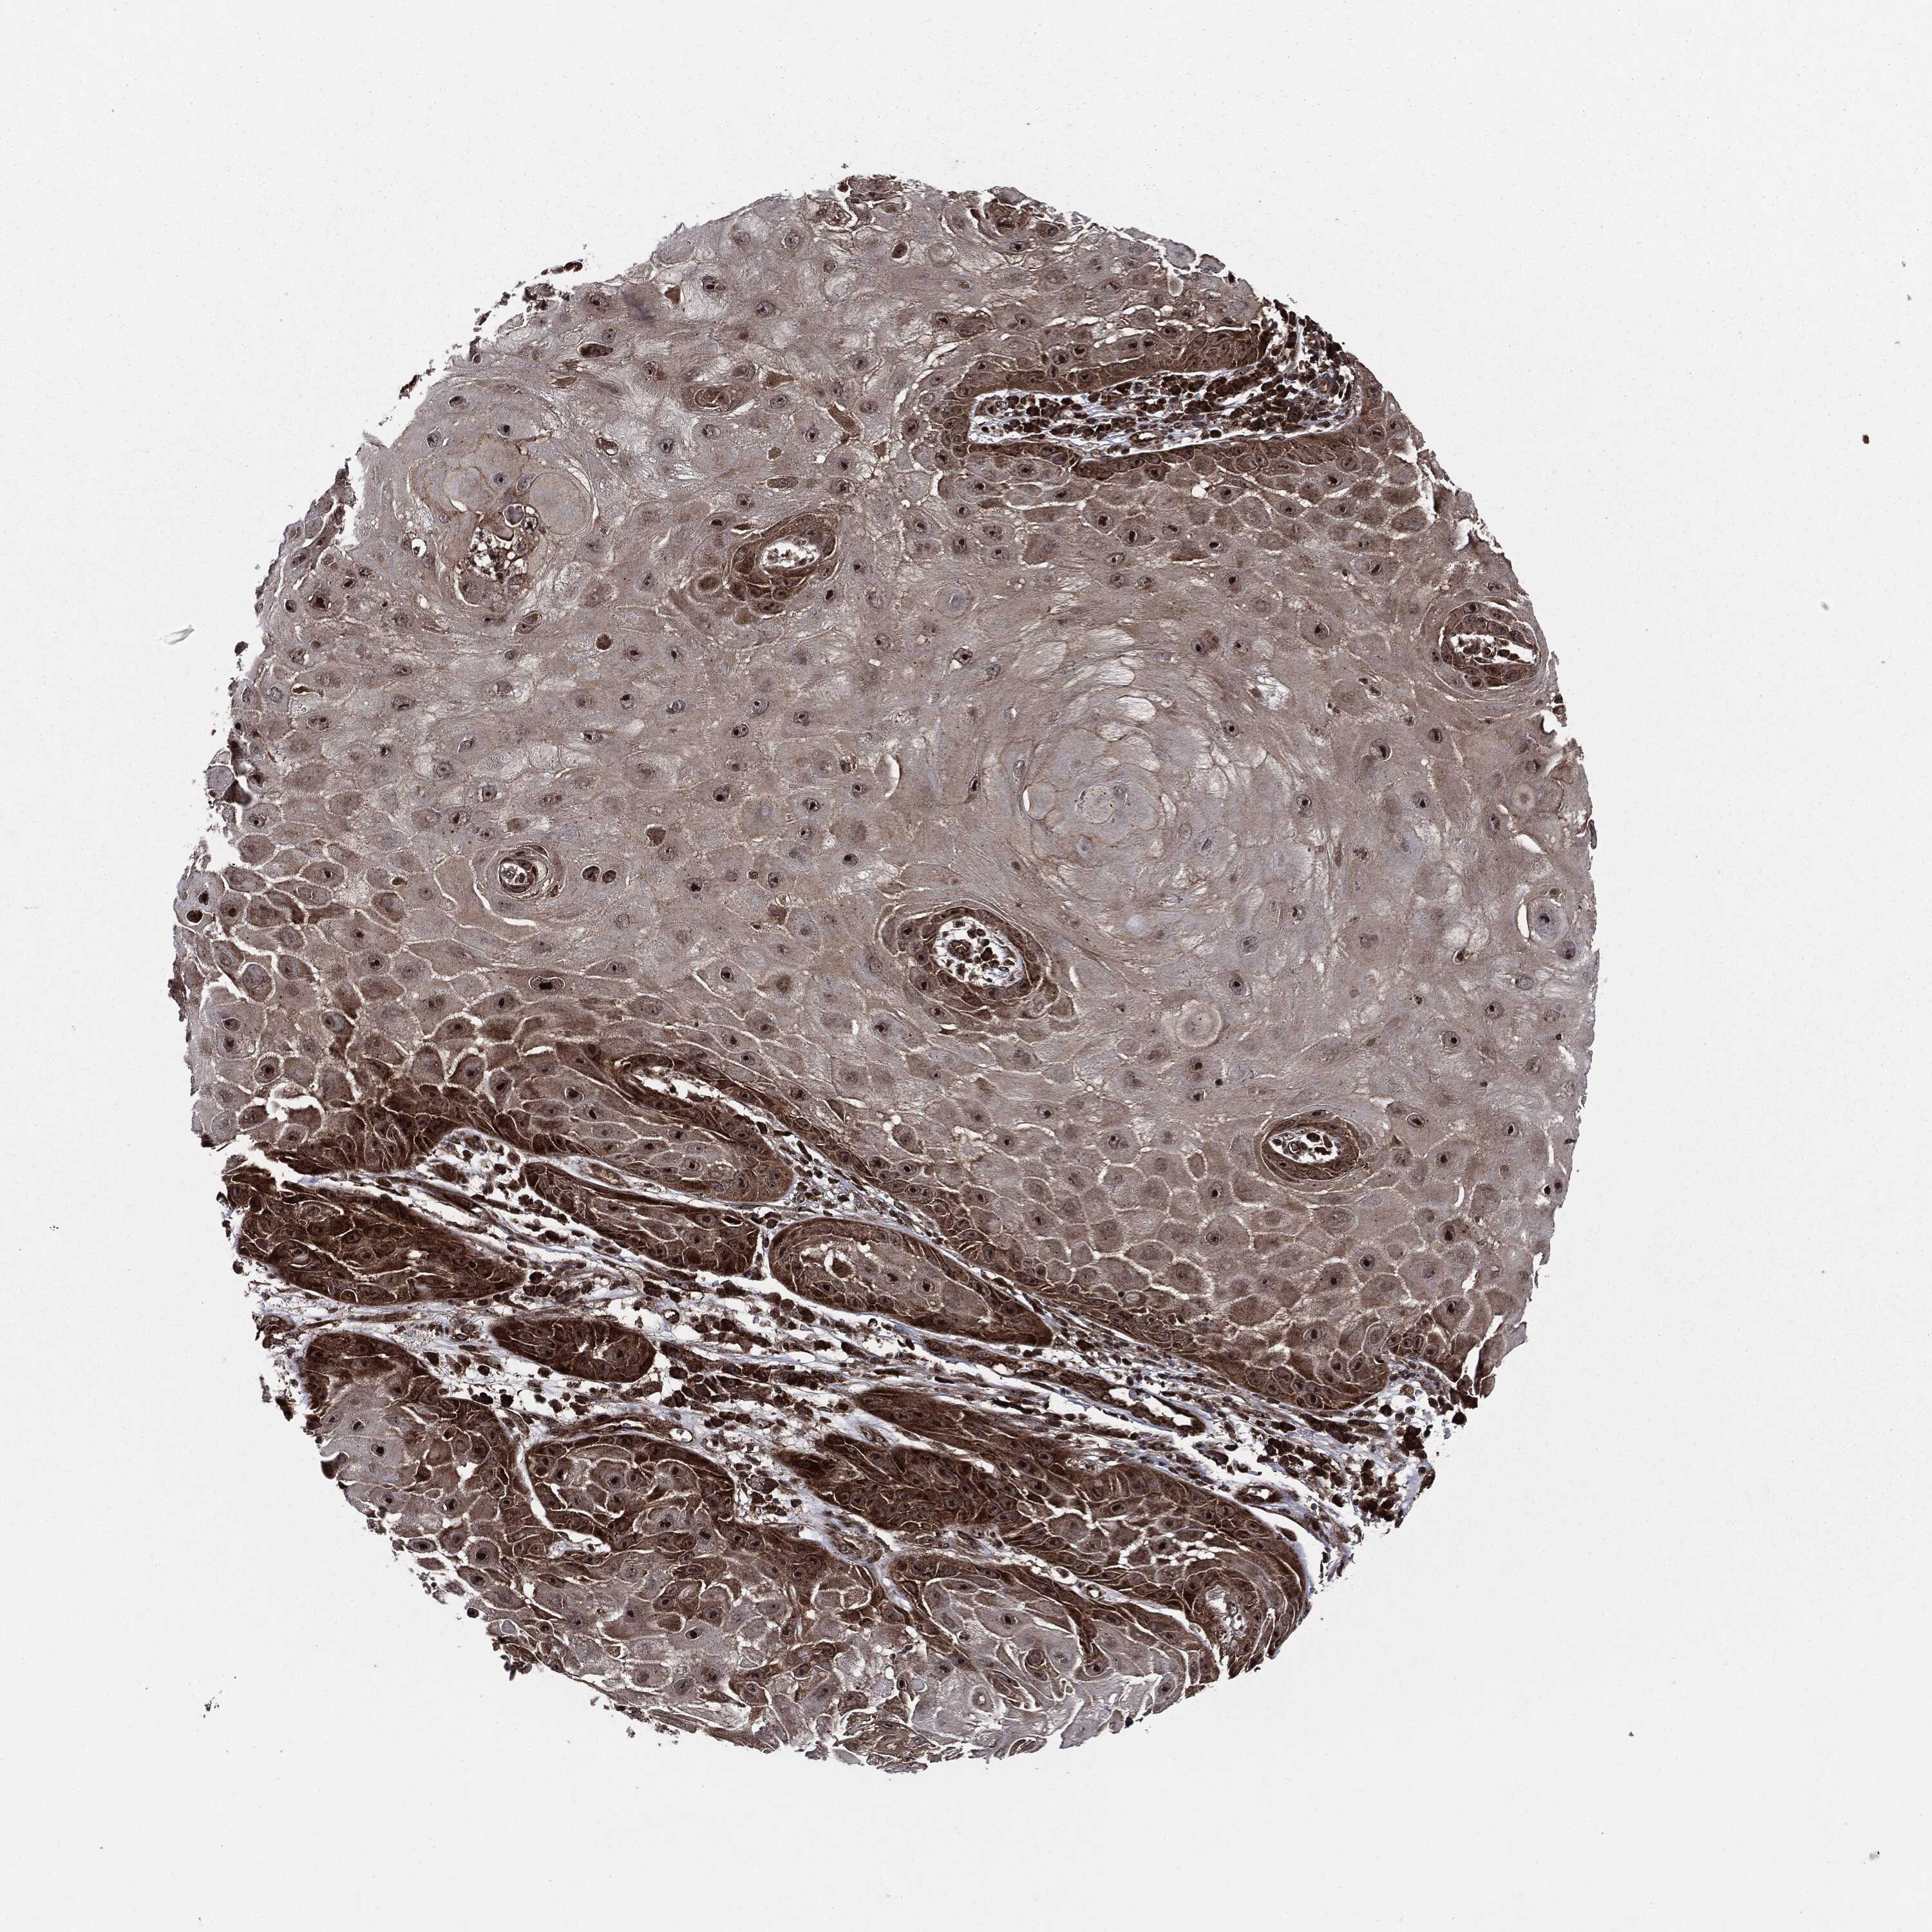

SKIN CANCER - Protein expressioni

A mouse-over function shows sample information and annotation data. Click on an image to view it in a full screen mode. Samples can be filtered based on level of antibody staining by selecting one or several of the following categories: high, medium, low and not detected. The assay and annotation is described here.

Antibody stainingi

Antibody staining in the annotated cell types in the current human tissue is reported as not detected, low, medium, or high, based on conventional immunohistochemistry profiling in selected tissues. This score is based on the combination of the staining intensity and fraction of stained cells.

Each image is clickable and will lead to virtual microscopy that enables deeper exploration of all samples and also displays staining intensity scores, fraction scores and subcellular localization as well as patient and tissue information for each sample.

Antibody HPA041933

Staining

High

Intensity

Strong

Quantity

>75%

Location

Nuclear

Basal cell carcinoma

Squamous cell carcinoma, NOS